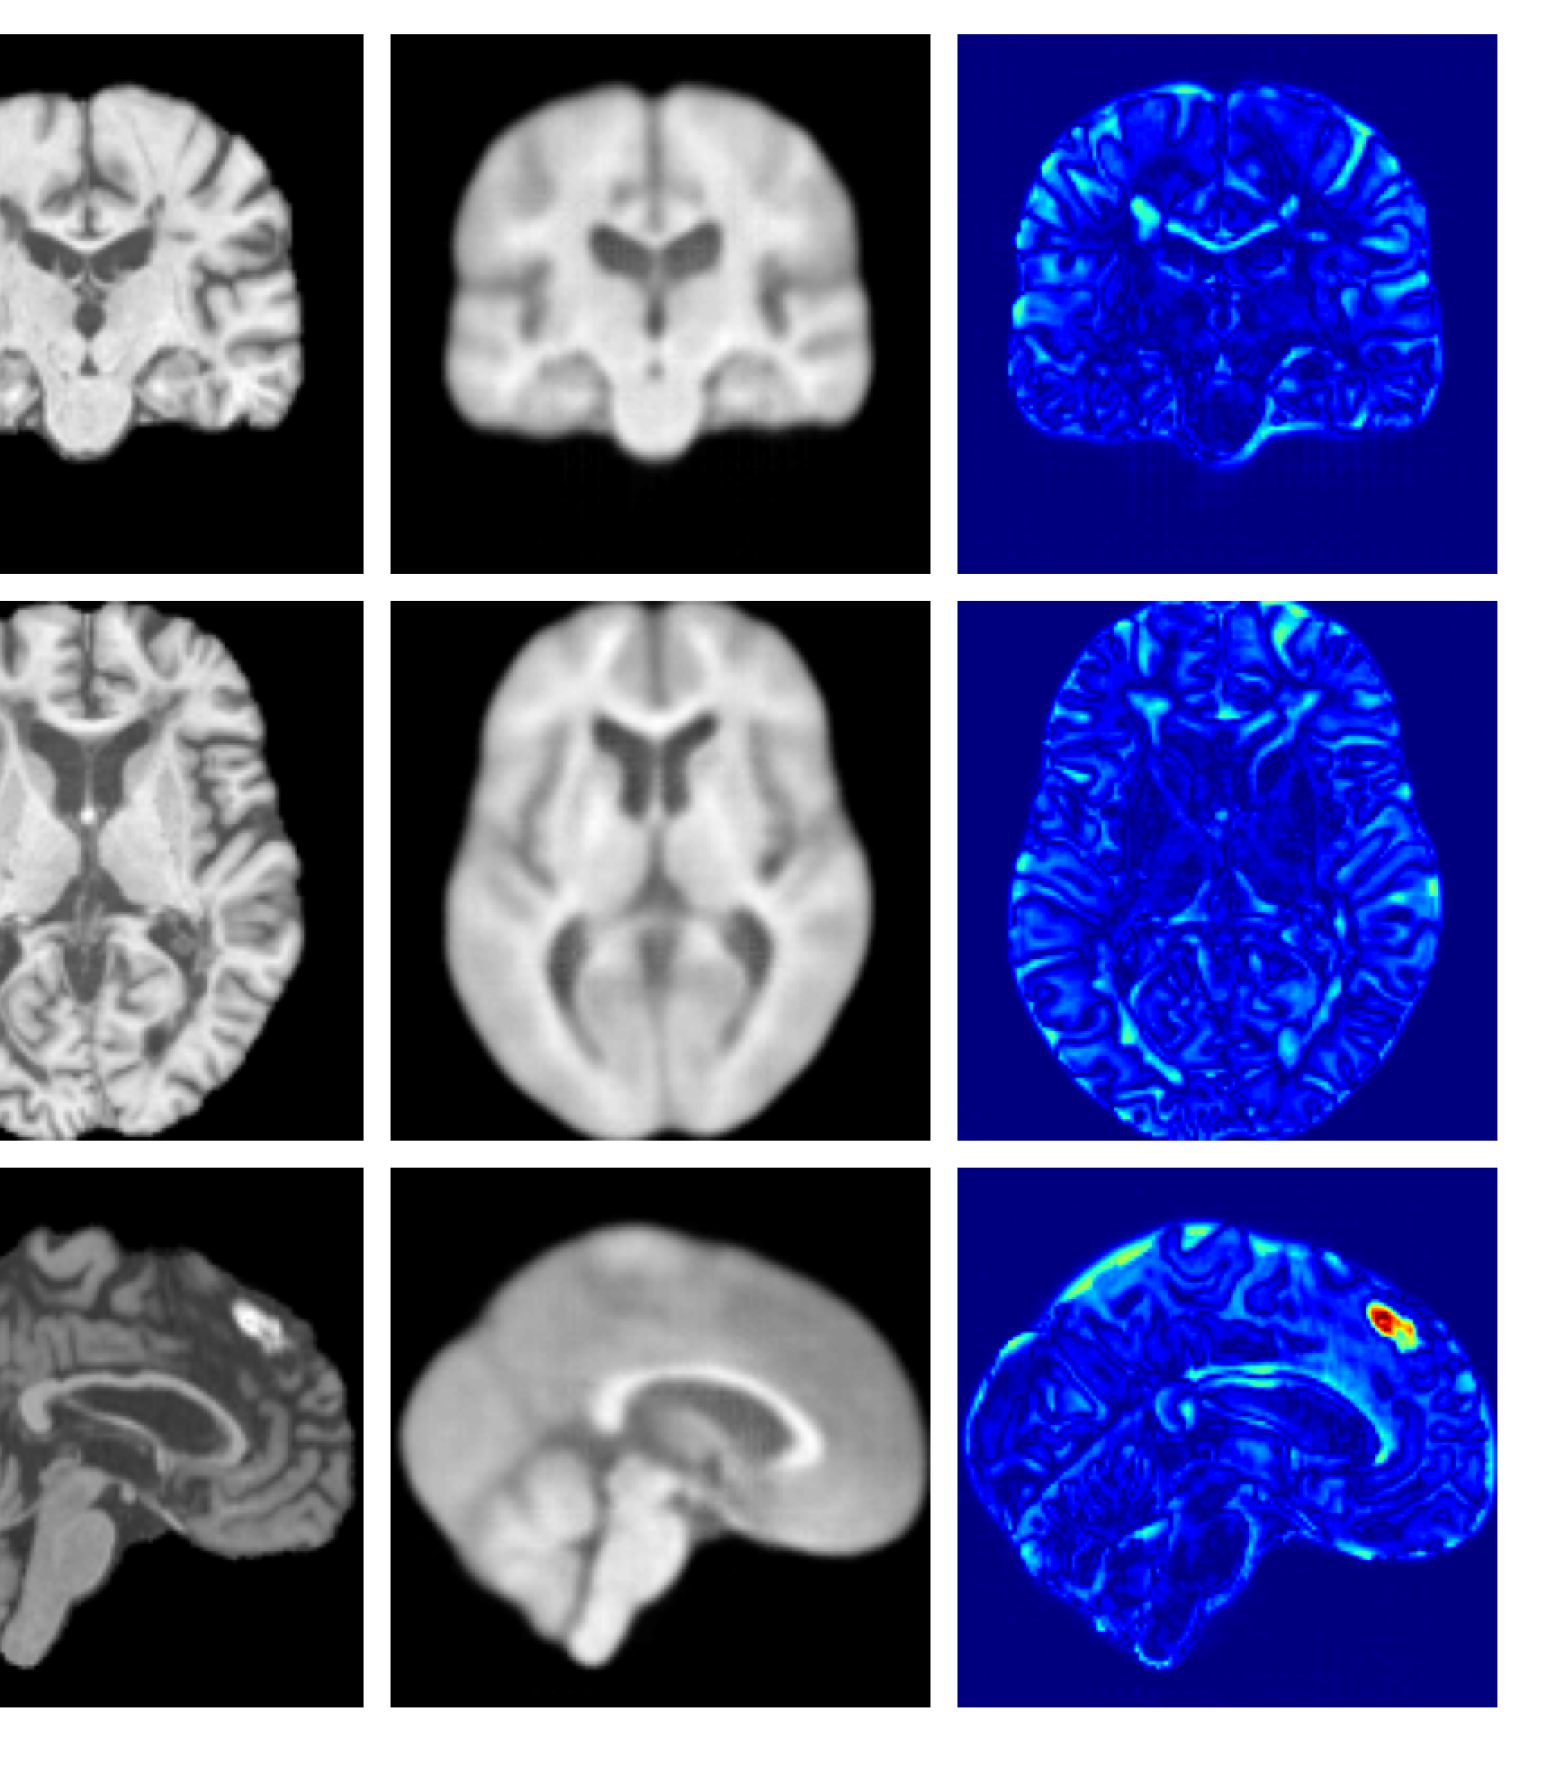

Figure 8: Enlarged example reconstructions and anomaly maps for a sample from the disease cohort of the UKBB dataset. Lesion and WMH are indicated in the original image by the red and yellow boxes respectively.

Figures 3 and 4, show example reconstructions and abnormality maps for a sample from the UKBB and UoTH datasets, respectively. Enlarged figures and additional example qualitative results for the ADNI dataset are available in the Supplementary. In Figure 3 we see that whilst all models are able to detect the lesion visible in the sagittal slice, the VAE, cVAE, LDM and LDM (TavgT_{avg}) produce very smooth outputs or lose defining characteristics and thus exhibit more false positives in healthy tissue. THOR and CADD provide the best results, with CADD better detecting white matter hypointensities (WMH). However, neither method fully inpaints all WMH, potentially due to presence of WMH in the healthy training set.

Figures 8 and 9 are enlarged versions of Figures 3 and 4 respectively, with the latter now including results from all compared methods. Figure 10 provides example reconstructions and anomaly maps for an AD subject from the ADNI disease cohort.